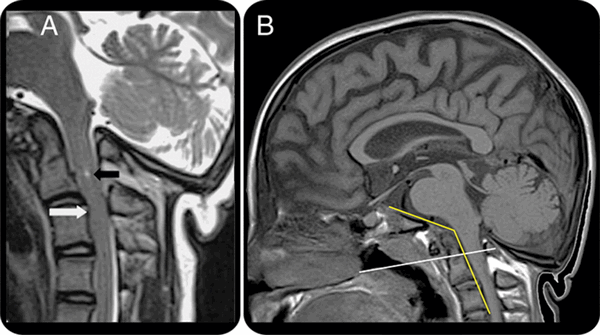

МРТ головного мозга в сагиттальной плоскости. Миндалины мозжечка пролабируют в большое затылочное отверстие (аномалия Арнольда-Киари). Спинной мозг обычной формы и размеров, контуры его ровные, четкие. Структура спинного мозга неоднородная за счет наличия на уровне тел С1-С3 позвонков в зоне сканирования в области центрального канала кистозного включения (сирингогидромиелическая киста). Признаков перифокального отека вещества спинного мозга не выявлено.

- Аномалия Арнольда-Киари. Изменение нормального анатомического положения продолговатого мозга и мозжечка. Врожденный патологический процесс, порок развития. Снимки краниовертебральной зоны позволяют оценить тяжесть расстройства, спланировать лечение.

МРТ краниовертебрального перехода. Краниовертебральный угол уменьшен до 125 гр. Угол Богарта увеличен до 127 гр. Зубовидный отросток С2 позвонка расположен на уровне линии Чемберлена. Признаки диспластических изменений краниовертебрального перехода — платибазия.